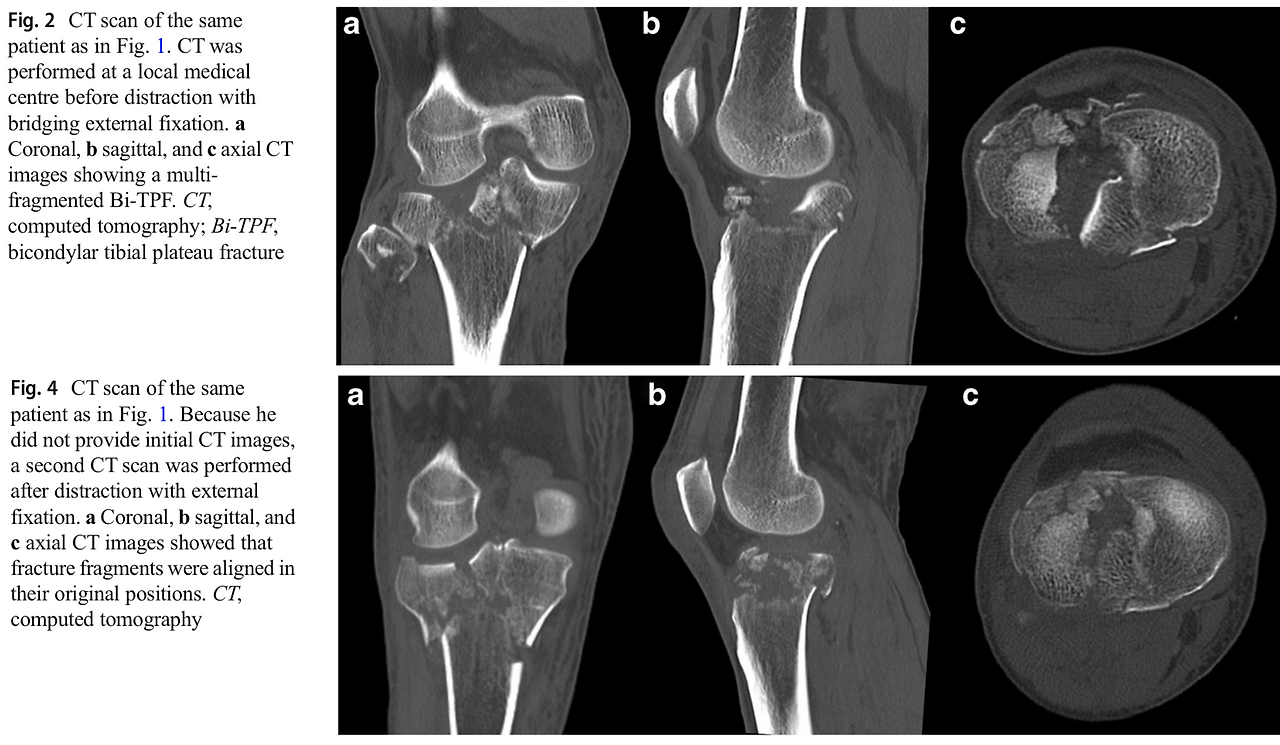

응급실로 경골 고원부 골절 환자가 내원을 했다면, 정형외과 전공의가 먼저 해야 하는 일은 X-ray를 확인한 다음, 골절의 형태를 파악하기 위해서 CT (전산화 단층촬영, computed tomography) 촬영을 진행해야 합니다. CT는 뼈의 3차원적인 모양을 파악하기에 좋은 검사이기 때문에, 수술을 위해서 필수적입니다.

손 교수님이 가끔 전공의들에게 불같이 화를 내실 때가 있었습니다. 그중에 하나가 경골 고원부 골절에 관한 처치였습니다. 만약 외고정술을 하기로 결정이 났다면, CT촬영을 외고정술을 하고 난 뒤에 진행하라고 늘 말씀하셨습니다. 왜냐하면 외고정술을 하고 무릎 주위 위아래로 약간 견인을 하면 뼈에 붙어 있는 인대와 같은 연부조직들이 원래 위치로 가려하기 때문에 뼛조각들이 원래 상태에 가깝게 정복이 되기 때문이었습니다. 이 개념이 전문 용어로는 ligamentotaxis라고 합니다. (사진 1)

traction_pre_post.png 사진 1. 외고정장치 적용 전(위) 후(아래) CT 영상 비교: 견인을 통한 정복을 보여주는 증례입니다.

몇 번 교수님께 혼나면서 배운 지식이고, 외고정장치로 견인을 하면 일시적으로 뼛조각이 맞추어지는 것을 저도 직관적으로 알 수 있었습니다. 하지만 과연 그게 과학적 근거가 있는지 궁금하였습니다. 인터넷에 찾아보았는데, 외고정장치를 적용하고 견인했을 때 뼛조각이 정렬된다는 원리는 잘 알려져 있었지만 ‘얼마나’ 좋아진다는 말이 없었습니다. (사진 2)

외고정술을 하지 않은 CT와 외고정술을 하고 난 뒤에 CT 두 그룹으로 나누어, 골절의 평가를 관찰자 일치도 연구를 통해 이를 객관적으로 검증해보고 싶었습니다. 이 연구는 동료 전공의들과 임상강사 선배님들이 참여하여 두 그룹의 골절 평가를 진행하기로 하였습니다.